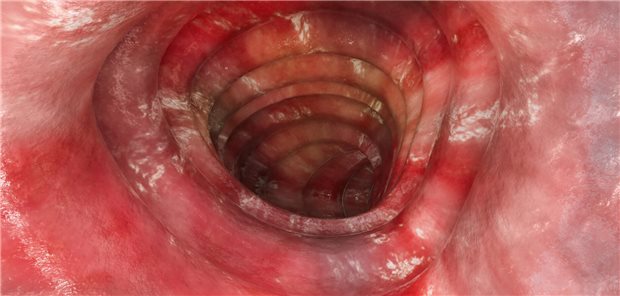

Ärzte führen eine Koloskopie durch. Die Patientin ist nur zu erahnen.

© Kzenon / stock.adobe.com

Prävention

Darmkrebs-Vorsorge: FIT versus Koloskopie – oder die Kombi?